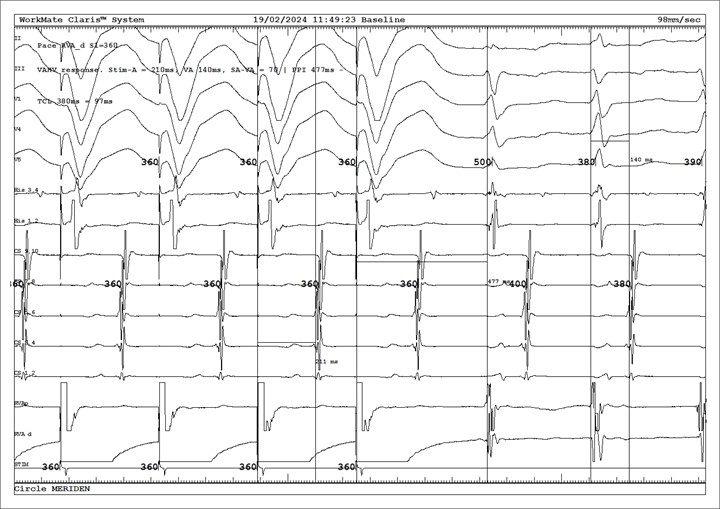

A lot of crucial information can be obtained from this image trace.

A continuation of the narrow complex tachycardia (NCT) can be observed from the last two beats on the right in Figure 1.

Three further observations can be made about the NCT:

Firstly, the ventriculo-atrial (VA) conduction time is long (140ms) which makes typical AVNRT (VA time <70ms) and junctional tachycardia very unlikely2.

Secondly, the atrial activation pattern is eccentric (earliest in CS 5-6/3-4). As the atrial activation pattern in AVNRT is concentric (CS proximal to distal, reflecting conduction through the AV node), this narrows down the differential diagnosis to either a left-sided AVRT or a left-sided AT.

Thirdly, the NCT has a 1:1 VA relationship. If this was not the case, then an AVRT could be ruled out. However in this case, the 1:1 VA relationship did not narrow down the differential diagnosis (AVRT vs AT).

The pacing manoeuvre is ventricular overdrive pacing (VOP) from the apex of the right ventricle, which is reflected in the first 4 beats (note the broad and negative QRS in V1 and superior axis). VOP is one of the most useful pacing manoeuvres to establish the mechanism of an NCT. SVT entrainment with manifest fusion was not seen in this case but its occurrence is proof that AVRT is present3.

An atrial-atrial-ventricular (or V-A-A-V) response is diagnostic of AT2. In this case, the response to VOP was V-A-V; which suggested either AVRT or atypical AVNRT (also unlikely in this case due to the aforementioned reasons). Two quantitative features of VOP can be observed which suggest AVRT:

- The difference between the post-pacing interval (PPI) and the TCL was 97ms (i.e PPI-TCL <115ms3 or corrected PPI-TCL<110ms)

- The difference between the stimulus to atrial electrogram (SA) interval and the tachycardia VA interval was 70ms (i.e SA-VA <85ms)

A corrected PPI-TCL <110ms and SA-VA <85ms suggests AVRT (as the ventricular pacing site is close to the tachycardia circuit)1.

In order to accurately interpret the response to VOP, it is important to confirm that the tachycardia was entrained in the first place. Entrainment is confirmed if the re-entrant tachycardia was reset by the series of consecutive beats of a pacing train (i.e VOP) with resumption of the tachycardia when VOP was discontinued4. In this case, the atrial cycle length during VOP matched the paced cycle length (360ms, which was faster than the TCL) and the tachycardia resumed upon discontinuation of VOP. It is also worth noting that the atrial activation during VOP was similar to that of the NCT (i.e eccentric which suggests retrograde atrial activation via a left-sided accessory pathway).

Electrocardiogram labels from top to bottom: Leads II, III, V1, V4, V5. His 3-4 (proximal), His 1-2 (distal), CS 9-10 (proximal) to CS 1-2 (distal), RVA proximal, RVA distal.